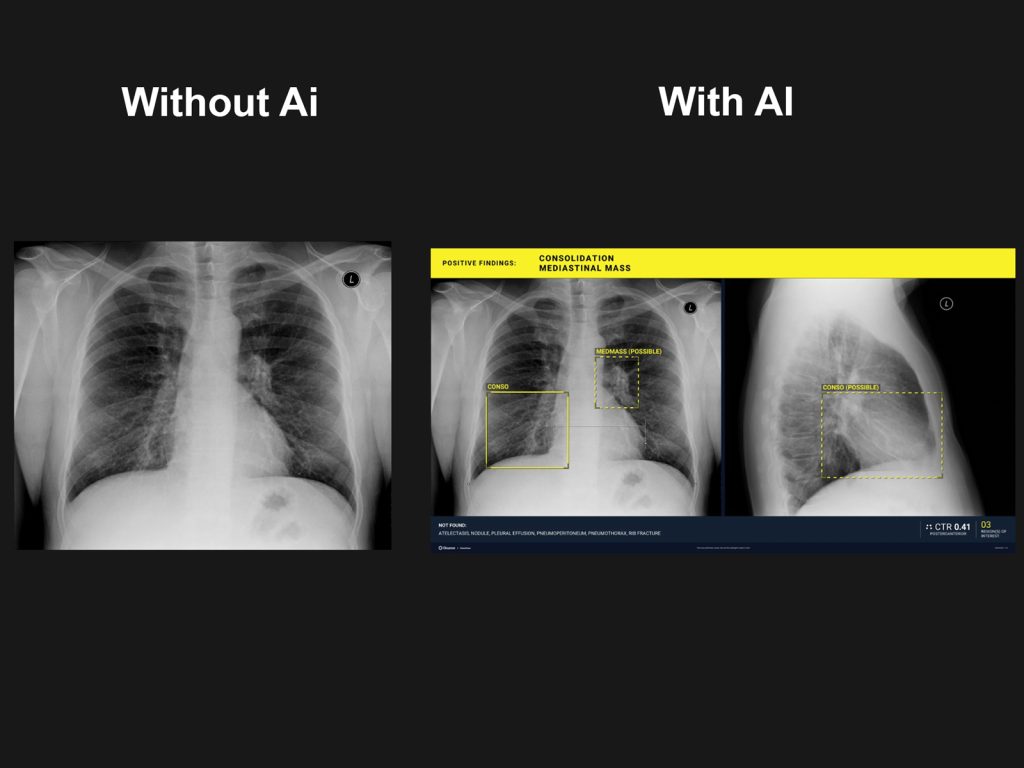

• Radiografia cu overlay, ce include markeri si denumiri ale patologiilor detectate, dupa cum vor fi descrise mai jos

• Zone suspecte marcate prin contur „bounding-box”

• Marcaje cu denumire pentru multiple leziuni (pneumonii, pneumotorax, noduli pulmonari, mase suspecte)

• Numar regiuni de interes

• Anomalii identificate (pozitive findings) vs anomalii neidentificate in studiu (negative findings)